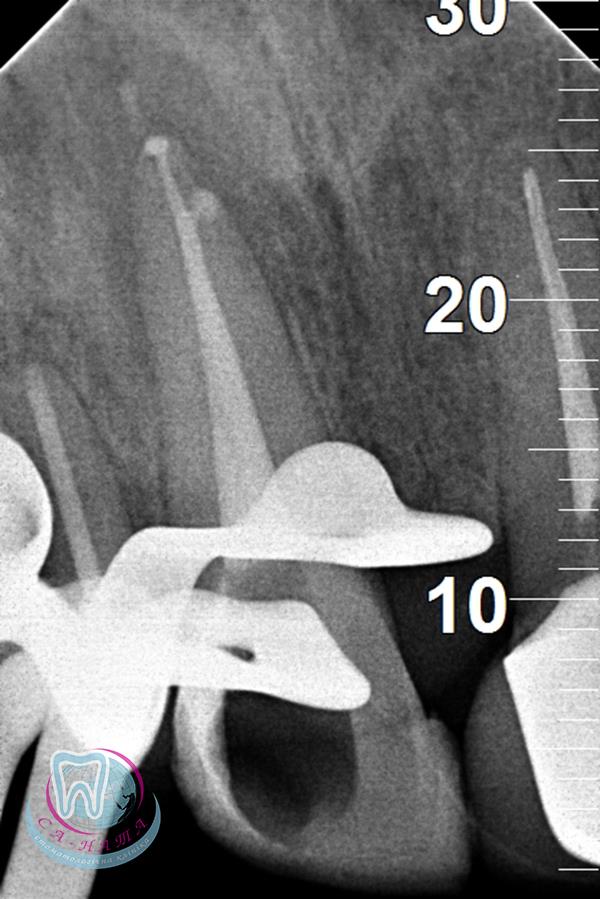

Today, radiological examination often plays a key role in dental care, as it allows us to see the anatomical structure of the teeth, their canals and roots, determine the condition of the jawbone tissue, assess the quality of the performed treatments, and analyze the dynamics of the treatment process.

To check the quality of root canal filling.

• Dental “targeted” X-ray.